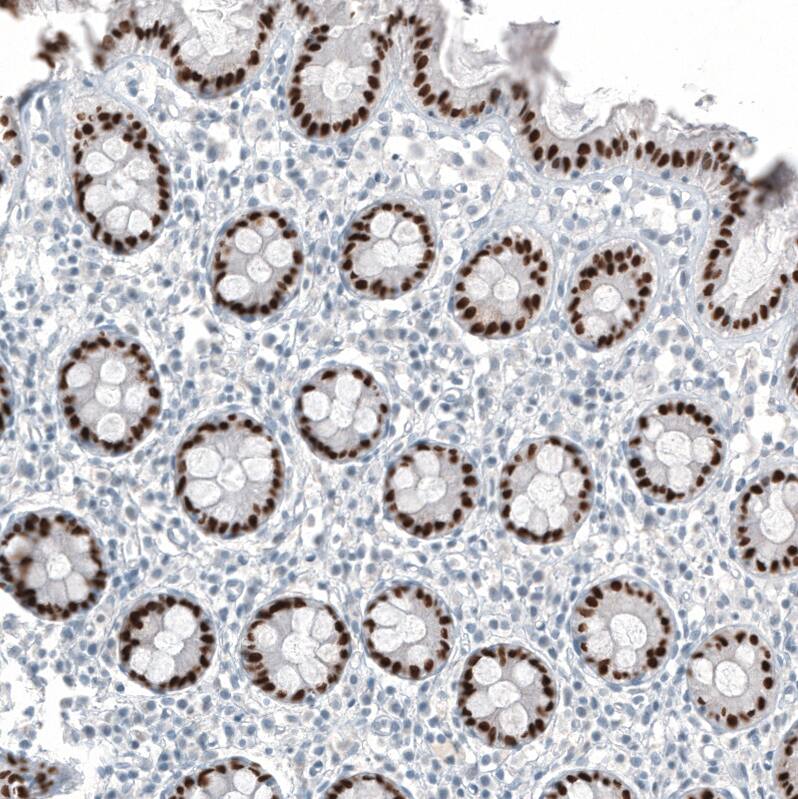

Staining of human colon shows moderate to strong nuclear positivity in glandular cells.

Staining of human rectum shows strong nuclear positivity in glandular cells.